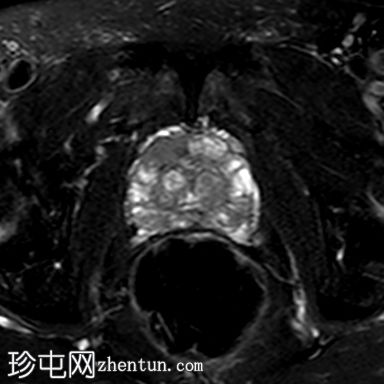

轴位

T2加权像

轴位T2加权像

脂肪抑制像

右侧前列腺前中带可见一边界不清的18 x 10 mm扁豆状病灶,T2加权像呈低信号,扩散受限(DWI高信号,ADC低信号),与周围实质相比早期强化,病灶位于前移行区与纤维肌性间质交界处。影像学表现符合PI-RADS 5级病灶。